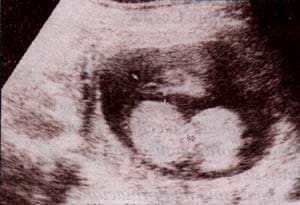

fig. 60. – (a). excencefalia. 18 semanas. se observa tejido cerebral flotando libremente en ausencia de calota. asociado un defecto lumbosacro. |

fig. 60. – (b). 25 semanas. corte frontal. es clara la ausencia de calota con tejido cerebral expuesto. |